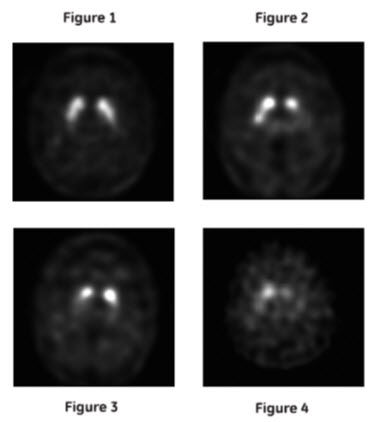

Normal: In transaxial images, normal images are characterized by two symmetric comma- or crescent-shaped focal regions of activity mirrored about the median plane. Striatal activity is distinct, relative to surrounding brain tissue (Figure 1).

Interpret DATSCAN images visually, based upon the appearance of the striata. Reconstructed pixel size should be between 3.5 mm and 4.5 mm with slices 1 pixel thick. Optimum presentation of the reconstructed images for visual interpretation is transaxial slices parallel to the anterior commissure-posterior commissure (AC-PC) line.

Determine whether an image is normal or abnormal by assessing the extent (as indicated by shape) and intensity of the striatal signal. Image interpretation does not involve integration of the striatal image appearance with clinical signs and/or symptoms.